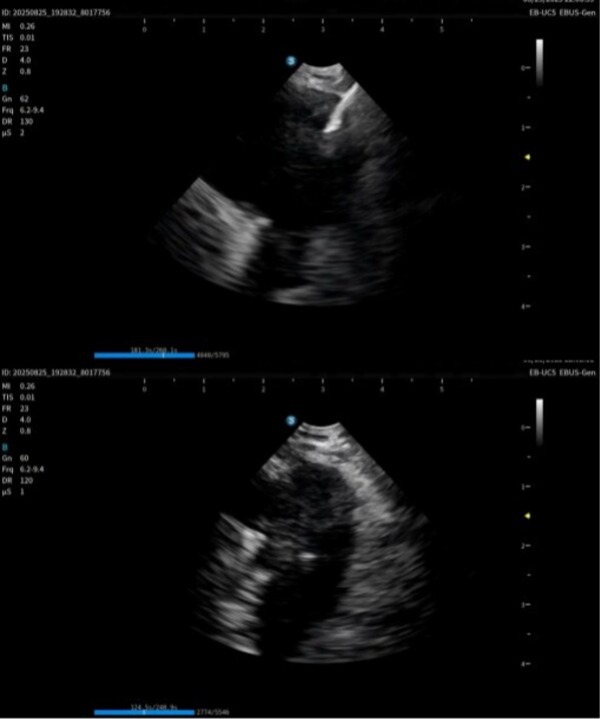

本次获证标志着开立医疗实现国内首家在该领域做到产品系列最齐,功能最完备的超声电子支气管内窥镜系统:超声电子支气管内窥镜+高清电子支气管镜+超声微探头+一体式超声内镜主机+分体式超声内镜主机,可满足不同呼吸诊疗术式临床应用需求。

作为在呼吸诊疗领域的重磅产品,本次在产品创新设计上和工艺技术上取得了重大突破,显著提升了光学图像和超声图像的质量,同时镜体保持了良好的操作性,在钳镜比和视野角综合参数可达到全球同类产品最佳性能。目前在临床应用表现突出,取得了专家的认可和好评。

超声电子支气管内窥镜凭借其"微创、精准、安全"的特点,已成为呼吸介入领域的核心技术之一。开立医疗全系列产品全面上市可为肺部肿瘤、纵隔病变提供管内清晰光学影像,管外高清声学断层组织及血流影像,提供精准可视化介入操作,为疾病的诊断提供更精准、更安全、更高效的一体化诊疗解决方案。